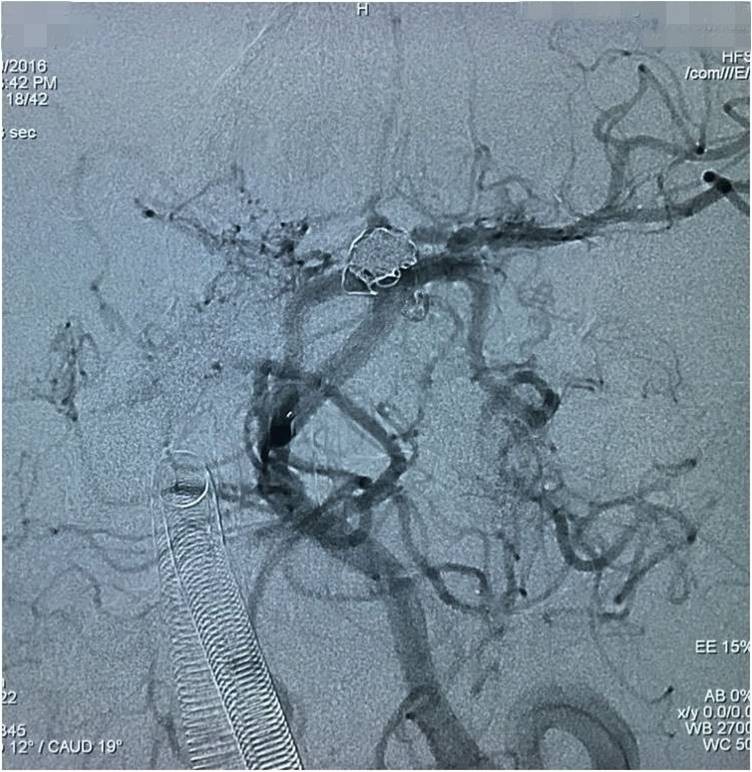

下面是术后各个角度的左椎动脉造影,可见基底动脉顶端动脉瘤和左小脑上动脉瘤完全栓塞,载瘤动脉畅通。基底动脉顶端动脉瘤的子瘤终于被消灭。

▼术后左椎动脉造影正位反汤28度。

▼纯正位。

▼侧位。

▼正位汤46度。